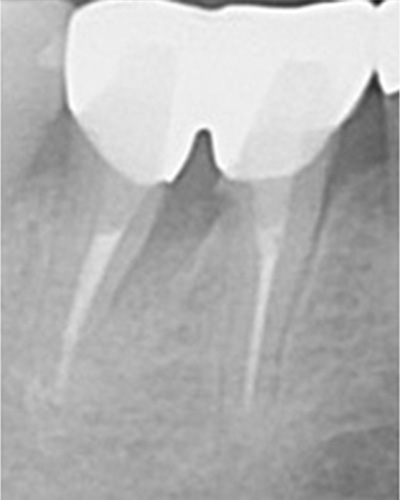

こちらのレントゲン写真を見てください。どちらかの歯医者さんで神経を取っています。根管に入れる薬は白く映ります。赤矢印部分です。一番右側が模式図ですが、青い部分が薬、根っこの先の赤点が化膿している部分です。

薬がほとんど入っていないのがわかります。黄矢印部分です。青矢印まで薬が入らないといけないのですが、全く入っていません。その結果、根っこの先が黒くなっています。膿が貯まって化膿すると黒く写ってくるのです。

別な歯科医院で治してもらいました。薬が根の先まで入っているのがわかります(黄矢印)。 根尖の黒い影が消失しています(赤矢印)。骨が再生すると白く写るようになります。

ガッタパーチャポイントは、理想的には歯根(シコン)の先ピッタリが良いと言われています。

上の図にあるように神経の管に入れる薬が根尖(コンセン)まで入っていなかったり、途中までしか入っていなかったり、薬がスカスカだったりするとその空間にばい菌が繁殖して感染を起こします。

①の写真はどちらかの歯医者さんで神経を取ってもらったレントゲン写真です。根っこの中に薬が全く入っていません。

根の先を見ると小豆ぐらいの大きさの黒い影が見えます。根の中でばい菌が繫殖し感染を起こすとこのような黒い影ができます。黒い影の部分は膿(ウミ)が貯まっています。こうなると腫れて痛みが出てくるのです。

③、④の写真はそれを治した後のレントゲン写真とその模式図です。白く映っている薬が根の先まできちんと入っているのが確認できます。そして根の先にあった黒い影が消えているのが分かります。根の先の炎症が治って、骨が再生すると白く映るのです。